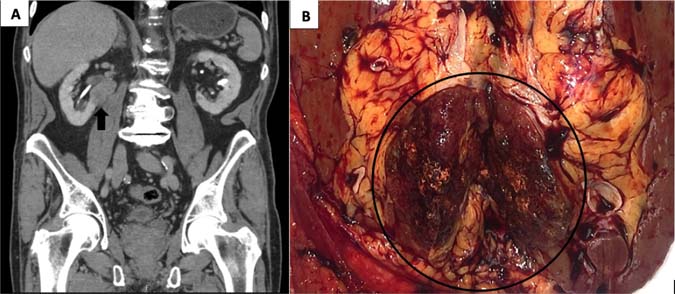

This 85-year-old white male initially presented at the age of 62 years with multiple cutaneous nodules in the head and neck region, diagnosed as multiple sebaceous adenomas. This prompted an investigation for visceral malignancies and genetic testing. Colonoscopy showed multiple tubular adenomas in the descending and sigmoid colon and high-grade dysplasia in the transverse colon. Genetic testing showed a pathogenic variant in MSH6 Exon 9 (c.3980_3983, dupATCA (p.L1330Vfs’12)). In addition a heterozygous novel variant of uncertain significance (c.8419A>G(p.T2807A) in the APC gene was also detected. Since he did not have the typical presentation of polyposis and lack of certainty regarding pathogenicity of the APC variant as well as presence of pathogenic variant in the MSH6 gene, a diagnosis of LS was made. Subsequently, multiple sebaceous adenomas were removed. At the age of 82 years, he presented with rectal bleeding and anemia. Abdominal computerized tomography scan showed a 6.8 × 6.6 × 8 cm mass in the right colon, and a 2.5 × 3.4 × 3.3 cm solid mass on the lower pole of the right kidney involving the hilum (Figure 1A), multiple hypodense nonenhancing lesions involving both lobes of the liver, and a 2.5 × 2.8 cm hypodense lesion in the body of the pancreas. The subsequent subtotal colectomy showed a T3N0 mucin-producing adenocarcinoma in the cecum. The wedge biopsy of the liver lesion at the same time showed a sclerosed hemangioma. The renal mass biopsy showed a PRCC. Three months later, a right nephrectomy was performed. Clinical follow-up 3 years after the resection shows multiple additional sebaceous adenomas involving the head and neck area and sebaceous carcinoma involving the eyelid. The pancreatic lesion is stable, and a biopsy was not performed. The timeline of the various tumors in this patient is shown in Table 1. There is no evidence of metastatic colon or RCC.

Figure 1: The Computerized Tomography (A) and the gross photograph (B) of the renal mass showing a well circumscribed tan brown mass in the right kidney extending into the renal hilum.

The pathological evaluation of the kidney showed a 3.4 × 3.3 × 3.0 cm well-circumscribed solid brown mass in the lower pole, extending into the hilum and perinephric fat (Figure 1B). Histologically, the tumor showed a mass without a capsule blending with the uninvolved renal parenchyma. Dense sclerotic stroma was present between clusters of tumor cells. The neoplasm showed a 90% papillary architecture with thin fibrovascular core, and occasional foamy histiocytes. The papillae were lined by a single layer of columnar cells with an abundant eosinophilic granular cytoplasm. The nucleus was low grade, round, and uniform with fine chromatin, placed away from the basal lamina without pseudostratification. The nuclear features were classified as ISUP grade 2. Focal areas of hemorrhage and cytoplasmic hemosiderin pigment in the tumor cells were present. Psammomatous calcification was absent (Figure 3A–F). IHC showed focal patchy positivity for AE1/AE3 and diffuse membranous staining for epithelial membrane antigen (EMA). There was a strong, diffuse cytoplasmic expression of vimentin, AMACR, luminal membranous expression of CD10, and nuclear expression of PAX8 (Figure 4A–F). The CAIX stain showed focal positivity. Cytokeratin 7 (CK7), high molecular weight cytokeratin, GATA3, and CD117 stains were negative in the tumor cells. These immunohistochemical features were most consistent with PRCC, type 2. IHC for mismatch repair proteins showed faint expression of MSH6 (1% of nuclei) and strong nuclear expression of MLH1, MSH2, and PMS2 (Figure 5A–D). The tumor was staged as T3a with sinus and perinephric fat invasion. Vascular invasion was not seen.